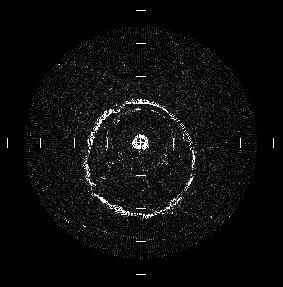

プラスチックの円筒の再構成画像を図に示す。

図中のスケールは2.5mm間隔である。

再構成画像では、プラスチック円筒の外径は1.1mmである。また、図の中心(図中の'

+')より少々左側に表示されているのはカテーテルの再構成像である。

図よりガラス円筒の大きさ、形ともに正確に再構成されていることが分かる。